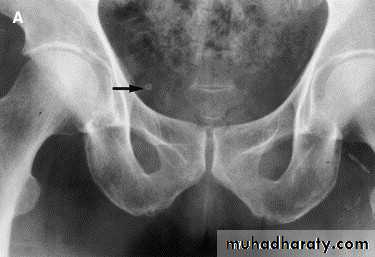

37- Phlebolith